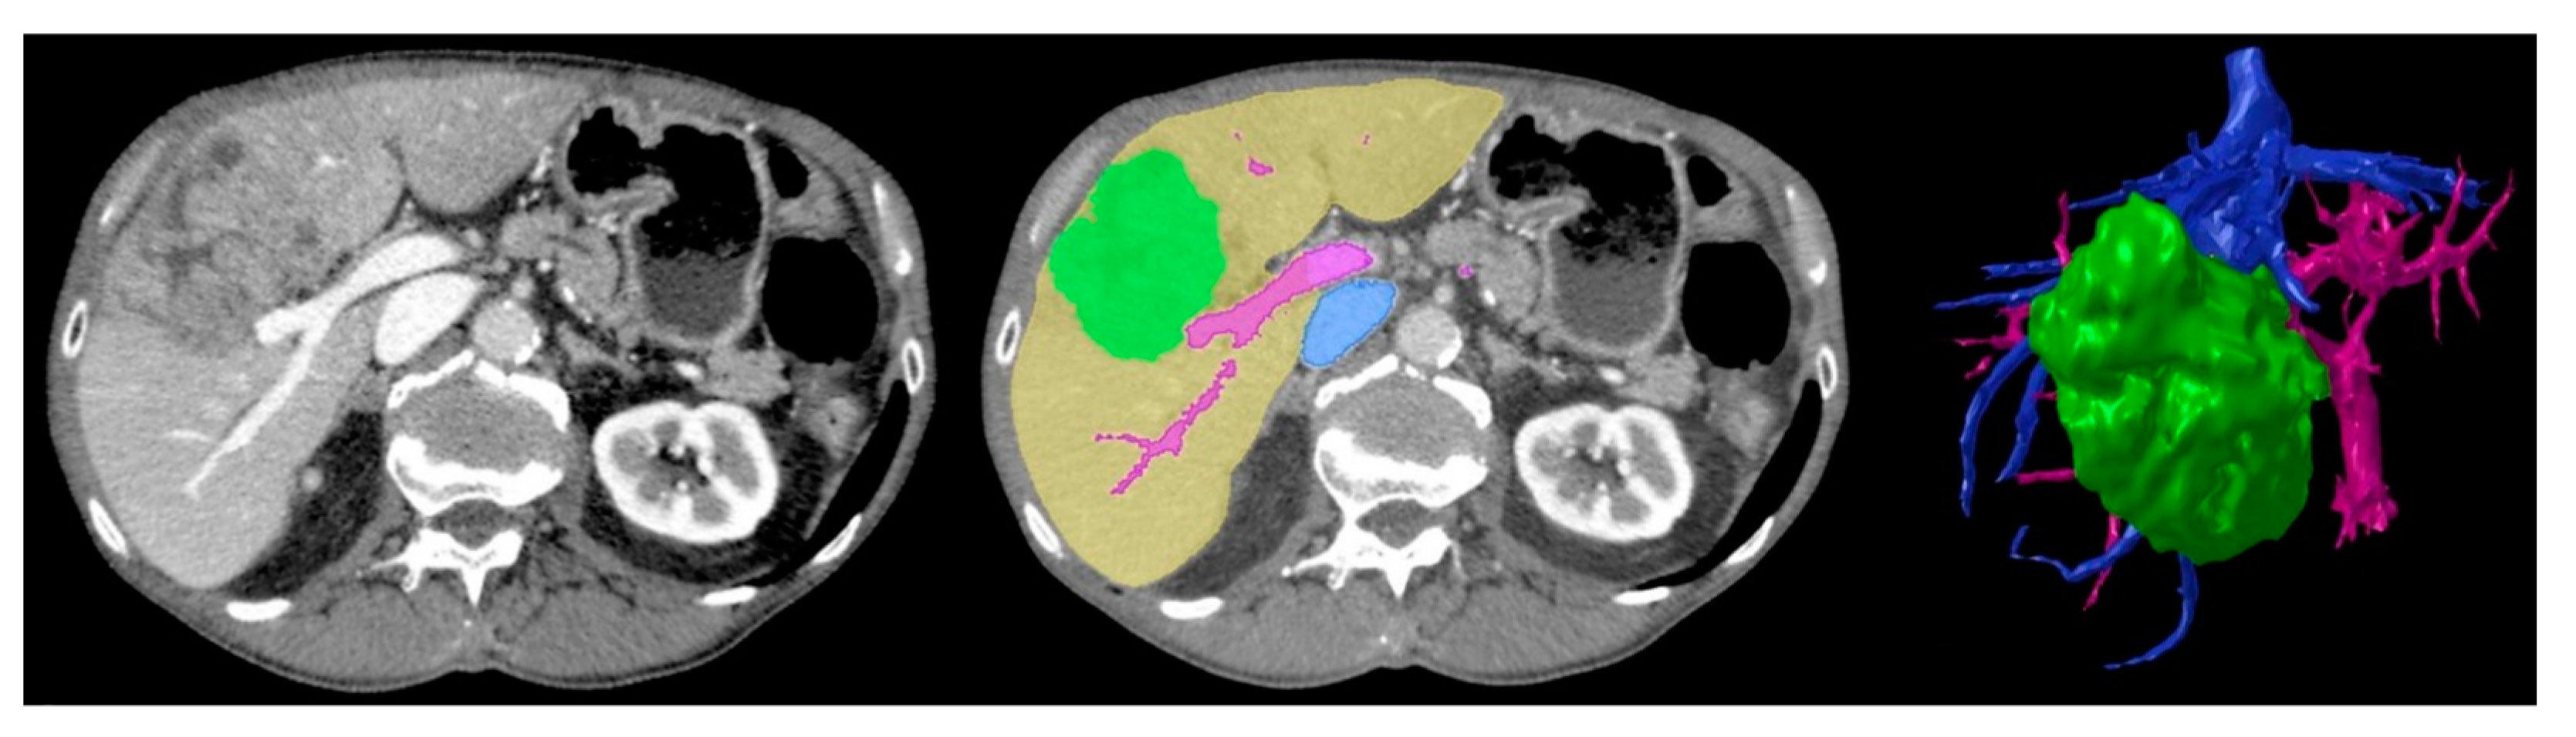

- Chen, J.; Bokacheva, L.; Rusinek, H. Image segmentation and nonuniformity correction methods. In 3D Printing for the Radiologist; Wake, N., Ed.; Elsevier: St. Louis, MO, USA, 2021; pp. 31–43. [Google Scholar]

- Gotra, A.; Sivakumaran, L.; Chartrand, G.; Vu, K.-N.; Vandenbroucke-Menu, F.; Kauffmann, C.; Kadoury, S.; Gallix, B.; de Guise, J.A.; Tang, A. Liver segmentation: Indications, techniques and future directions. Insights Imaging 2017, 8, 377–392. [Google Scholar] [CrossRef]